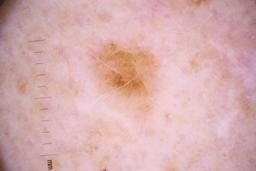

ISIC_4077341

Public

Information

- Created

- Dimensions

- 5184 x 3456

- Attribute to

- The University of Queensland Diamantina Institute, The University of Queensland, Dermatology Research Centre

- License

- CC-BY

- Used in

- Challenge 2020: Training

- Belongs to

- IP_1969685 IL_9238622

Clinical

| Field | Value |

|---|---|

| acquisition_day | 1 |

| age_approx | 50 |

| anatom_site_1 | Trunk |

| anatom_site_2 | Anterior trunk |

| concomitant_biopsy | False |

| dermoscopic_type | contact non-polarized |

| diagnosis_1 | Benign |

| diagnosis_confirm_type | serial imaging showing no change |

| family_hx_mm | False |

| image_type | dermoscopic |

| lesion_id | IL_9238622 |

| patient_id | IP_1969685 |

| personal_hx_mm | True |

| sex | male |

Columns

Showing first 50 images.